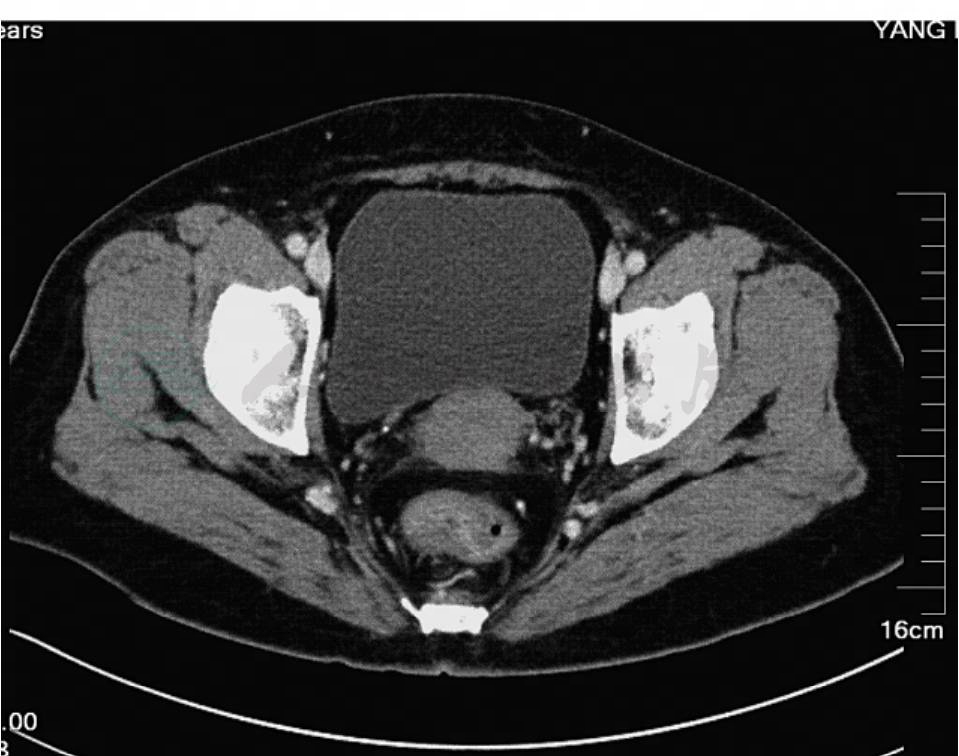

肠镜:距肛缘6cm可见环周不规则隆起,活检病理诊断直肠腺癌。CT:直肠肿物考虑恶性,肠系膜周围有肿大淋巴结(图1)。

图1 术前CT图像